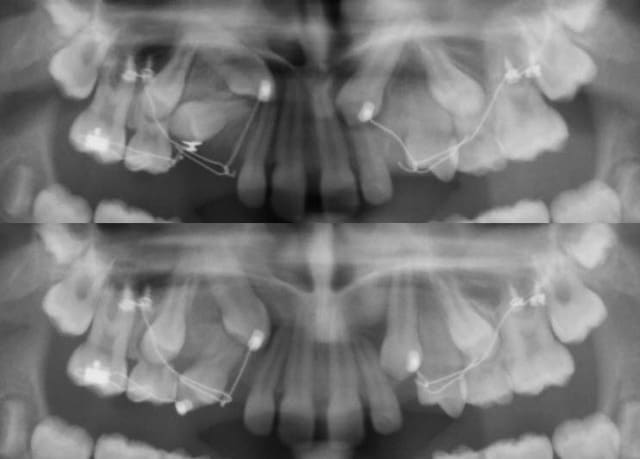

C'est parti !

Des CT8-1 pour tracter 13 et 23, un arc en TMA .016 comme l'a décrit Seespan pour tracter 14.

J'ai quand même collé un tube en vestibulaire de 16 par simplicité.

Le fil collé sur 55 passe dans le tube en direction distale, est replié en "U" pour revenir en mésial faire son action.

12224 1 i54xex - Eugenol